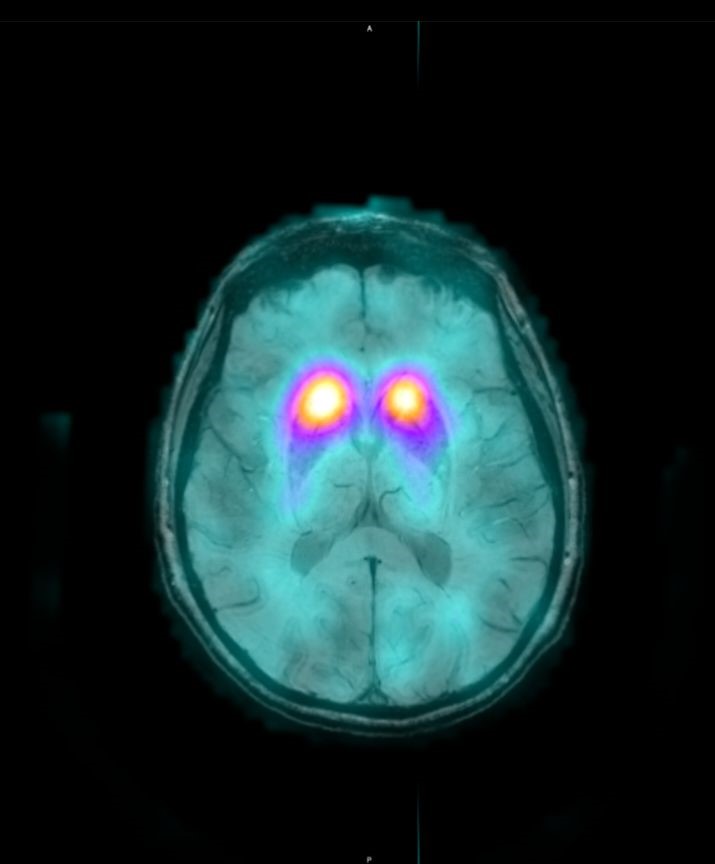

Το Lu-177 PSMA αποτελεί μια στοχευμένη ραδιονουκλιδική θεραπεία για ασθενείς με ορμονοάντοχο μεταστατικό καρκίνο του προστάτη (mCRPC), αξιοποιώντας τη υπερέκφραση του PSMA (Prostate-Specific Membrane Antigen) στα καρκινικά κύτταρα. Προηγείται PSMA PET/CT για ακριβή χαρτογράφηση της νόσου και επιβεβαίωση επαρκούς πρόσληψης του ραδιοφάρμακου. Το Lu-177 PSMA συνδέεται στους PSMA-υποδοχείς, επιτρέποντας στοχευμένη ακτινική δράση υψηλής κυτταροτοξικότητας σε μεταστατικές εστίες οστών και μαλακών μορίων. Η χρήση εξειδικευμένων δοσιμετρικών εργαλείων επιτρέπει την ποσοτική αποτίμηση της δόσης σε κρίσιμα όργανα (π.χ. σιελογόνοι αδένες, νεφροί, μυελός) και στον όγκο, συμβάλλοντας σε εξατομικευμένη θεραπευτική προσέγγιση. Μετά από κάθε κύκλο πραγματοποιείται PSMA PET/CT ή FDG PET/CT (όπου ενδείκνυται), καθώς και στενός αιματολογικός έλεγχος για αξιολόγηση της ανταπόκρισης και των πιθανών τοξικοτήτων. Η θεραπεία έχει αποδειχθεί ιδιαίτερα αποτελεσματική στη μείωση του καρκινικού φορτίου, στη βελτίωση του πόνου, στη μείωση των επιπέδων PSA και στη σημαντική παράταση του προσδόκιμου επιβίωσης σε ασθενείς με εκτεταμένη και ανθεκτική νόσο.

Με τη SPECT‑CT ποσοτικοποίηση υπολογίζουμε απορροφούμενες δόσεις σε όγκους και όργανα‑στόχους (νεφροί, σιελογόνοι, ήπαρ, μυελός κ.ά.). Αυτό:

Με βάση τα σύγχρονα Guidelines όλων των διεθνών ογκολογικών εταιρειών η μεταθεραπευτική απεικόνιση είναι προαπαιτούμενο για την έναρξη-συνέχιση της θεραπείας και το βέλτιστο αποτέλεσμα αυτής.